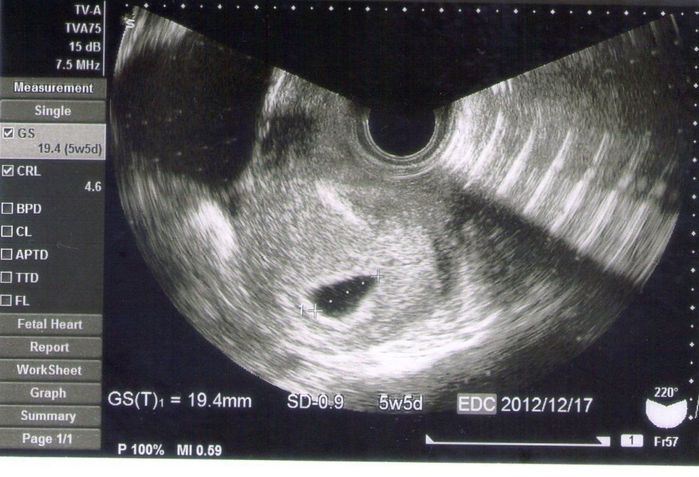

妊娠5週目のエコー写真 妊娠判明

GS=19.4㎜

生理が遅れ、ときどき吐き気を感じたことから市販の妊娠検査薬で確認したところ、陽性反応だったため、病院へ。エコー画像の真ん中に、赤ちゃんのいる袋(胎嚢)が写っていました。新しい命を授かった嬉しさで胸がいっぱい。しかし、ひどいつわりと眠気に悩まされる日々が始まりました。その頃はあまり食事がとれなくて、イオン飲料やゼリー飲料を飲みながら、どうにか栄養摂取している状態でした。